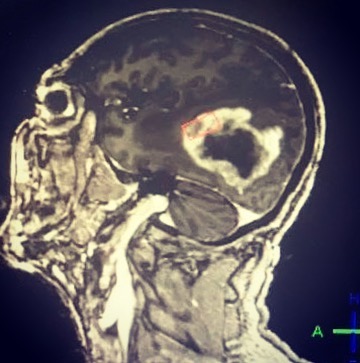

Cirugías neurológicas

Cirugía epilepsia

Cirugía aneurisma cerebral

Cirugía tumores cerebrales

Cirugía para hidrocefalia